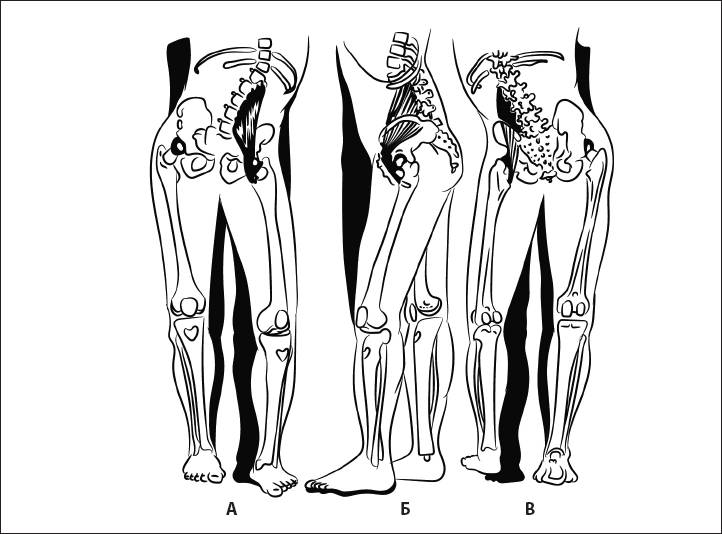

Рис. 32. Укорочение пояснично-подвздошной мышцы. А – вид спереди, Б – вид сбоку, В – вид сзади.

Биомеханика. Коленный сустав в разогнутом состоянии обеспечивает стабилизацию ноги при опоре на нее. Визуальные критерии – разгибание коленного сустава.

Ошибка. Сгибание коленного сустава и опора на полусогнутый сустав. Причина – в гипотонии четырехглавой мышцы бедра и укорочении пояснично-подвздошной мышцы, разгибателей бедра (рис. 32). В результате нарушается стабильность таза и коленного сустава, происходит перегрузка менисков коленного сустава в зависимости от локализации компенсаторно-перегруженной мышцы.

Биомеханика. Тазобедренный сустав сгибается строго по вертикальной линии без отклонений в сторону. Большую роль в его стабилизации в вертикальном положении играет пояснично-подвздошная мышца. В зависимости от ее исходного состояния изменяется нагрузка на сустав (рис. 38, 39) и неправильно формируется его сгибание (рис. 33, 34).

Ошибка 1. Сгибание в суставе сочетается с наружным разворотом ноги так, что пальцы стопы смещены кнаружи от пятки. Причина – укорочение пояснично-подвздошной мышцы (рис. 38).

Рис. 38. Экстензия бедра с укорочением пояснично-подвздошной мышцы. А – вид сзади, Б – вид сбоку.

Ошибка 2. Вместо сгибания в тазобедренном суставе происходит сгибание в коленном или поясничном регионе; пальцы стопы относительно пятки смещаются вовнутрь. Причина – гипотония пояснично-подвздошной мышцы (рис. 39).

Ошибка 3. Сгибание ноги сопровождается разворотом таза.

Рис. 39. Гипотония пояснично-подвздошной мышцы. А – вид спереди, Б – вид сбоку, В – вид сзади.